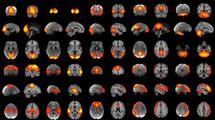

Scientists have voiced their serious concerns over major pharmaceutical companies' abrupt withdrawal from research into mental illness and neurological diseases. Coupled with low levels of neuroscience research funding, this could mean that fewer new treatments are developed for people with conditions such as depression, anxiety, schizophrenia, Parkinson's disease and Alzheimer's. A report, written by Professor Guy Goodwin of Oxford University and Professor David Nutt of Imperial College for the European College of Neuropsychopharmacology, states that 'the withdrawal of research resources is a withdrawal of hope for patients and their families'. Professor Guy Goodwin of Oxford University's Department of Psychiatry said: 'The issue here is not just that a very key part of Europe's knowledge economy is under serious threat, it's that the withdrawal of research resources means the slow down - and even outright cessation in some areas - of new treatments being developed, and this will inevitably affect patient well-being.' Around one in three people in Europe is estimated to suffer from one or more of these conditions in any year. Highly prevalent disorders such as depression, dementia and addiction are thought to now account for some 35% of Europe's total disease burden - that's higher than cancer or heart disease. 'Despite the public health imperative, not only has EU research funding remained very low, but - even worse - big pharma is increasingly coming to see research into better neuropsychiatric drug targets as economically non-viable,' said Professor David Nutt.